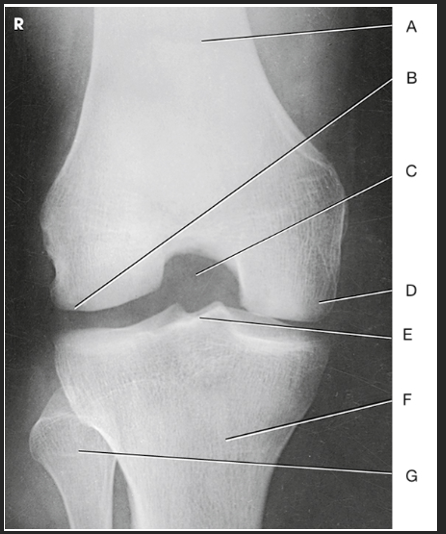

Name this projection.

AP axial IC Fossa

Name the method used.

Béclére Method

How do you know this image is a Beclere Method

Marker (line yourself up... only AP IC fossa) and is the smallest unilateral IC fossa (not elongated like Camp-Coventry and not as big as Holmblad)

Label the image: A

femur

Label the image: B

lateral condyle

Label the image: C

intercondylar fossa

Label the image: D

medial condyle

Label the image: E

intercondylar eminence

Label the image: F

tibia

Label the image: G

fibula

How does the IC fossa appear in the AP axial projection compared to the PA axial projection? (What sets the Beclere apart from the Holmblad/Camp-Coventry images?)

In Merrill's, the Beclere method makes the IC fossa look smaller. However, because we no longer have 10x12cassettes, we are forced clinically to have a larger OID in the AP axial projection, making the image look magnified compared to the PA axial projections

What are all three projections of the IC fossa looking for?

An open IC fossa (where the patellar apex is not superimposing the fossa)